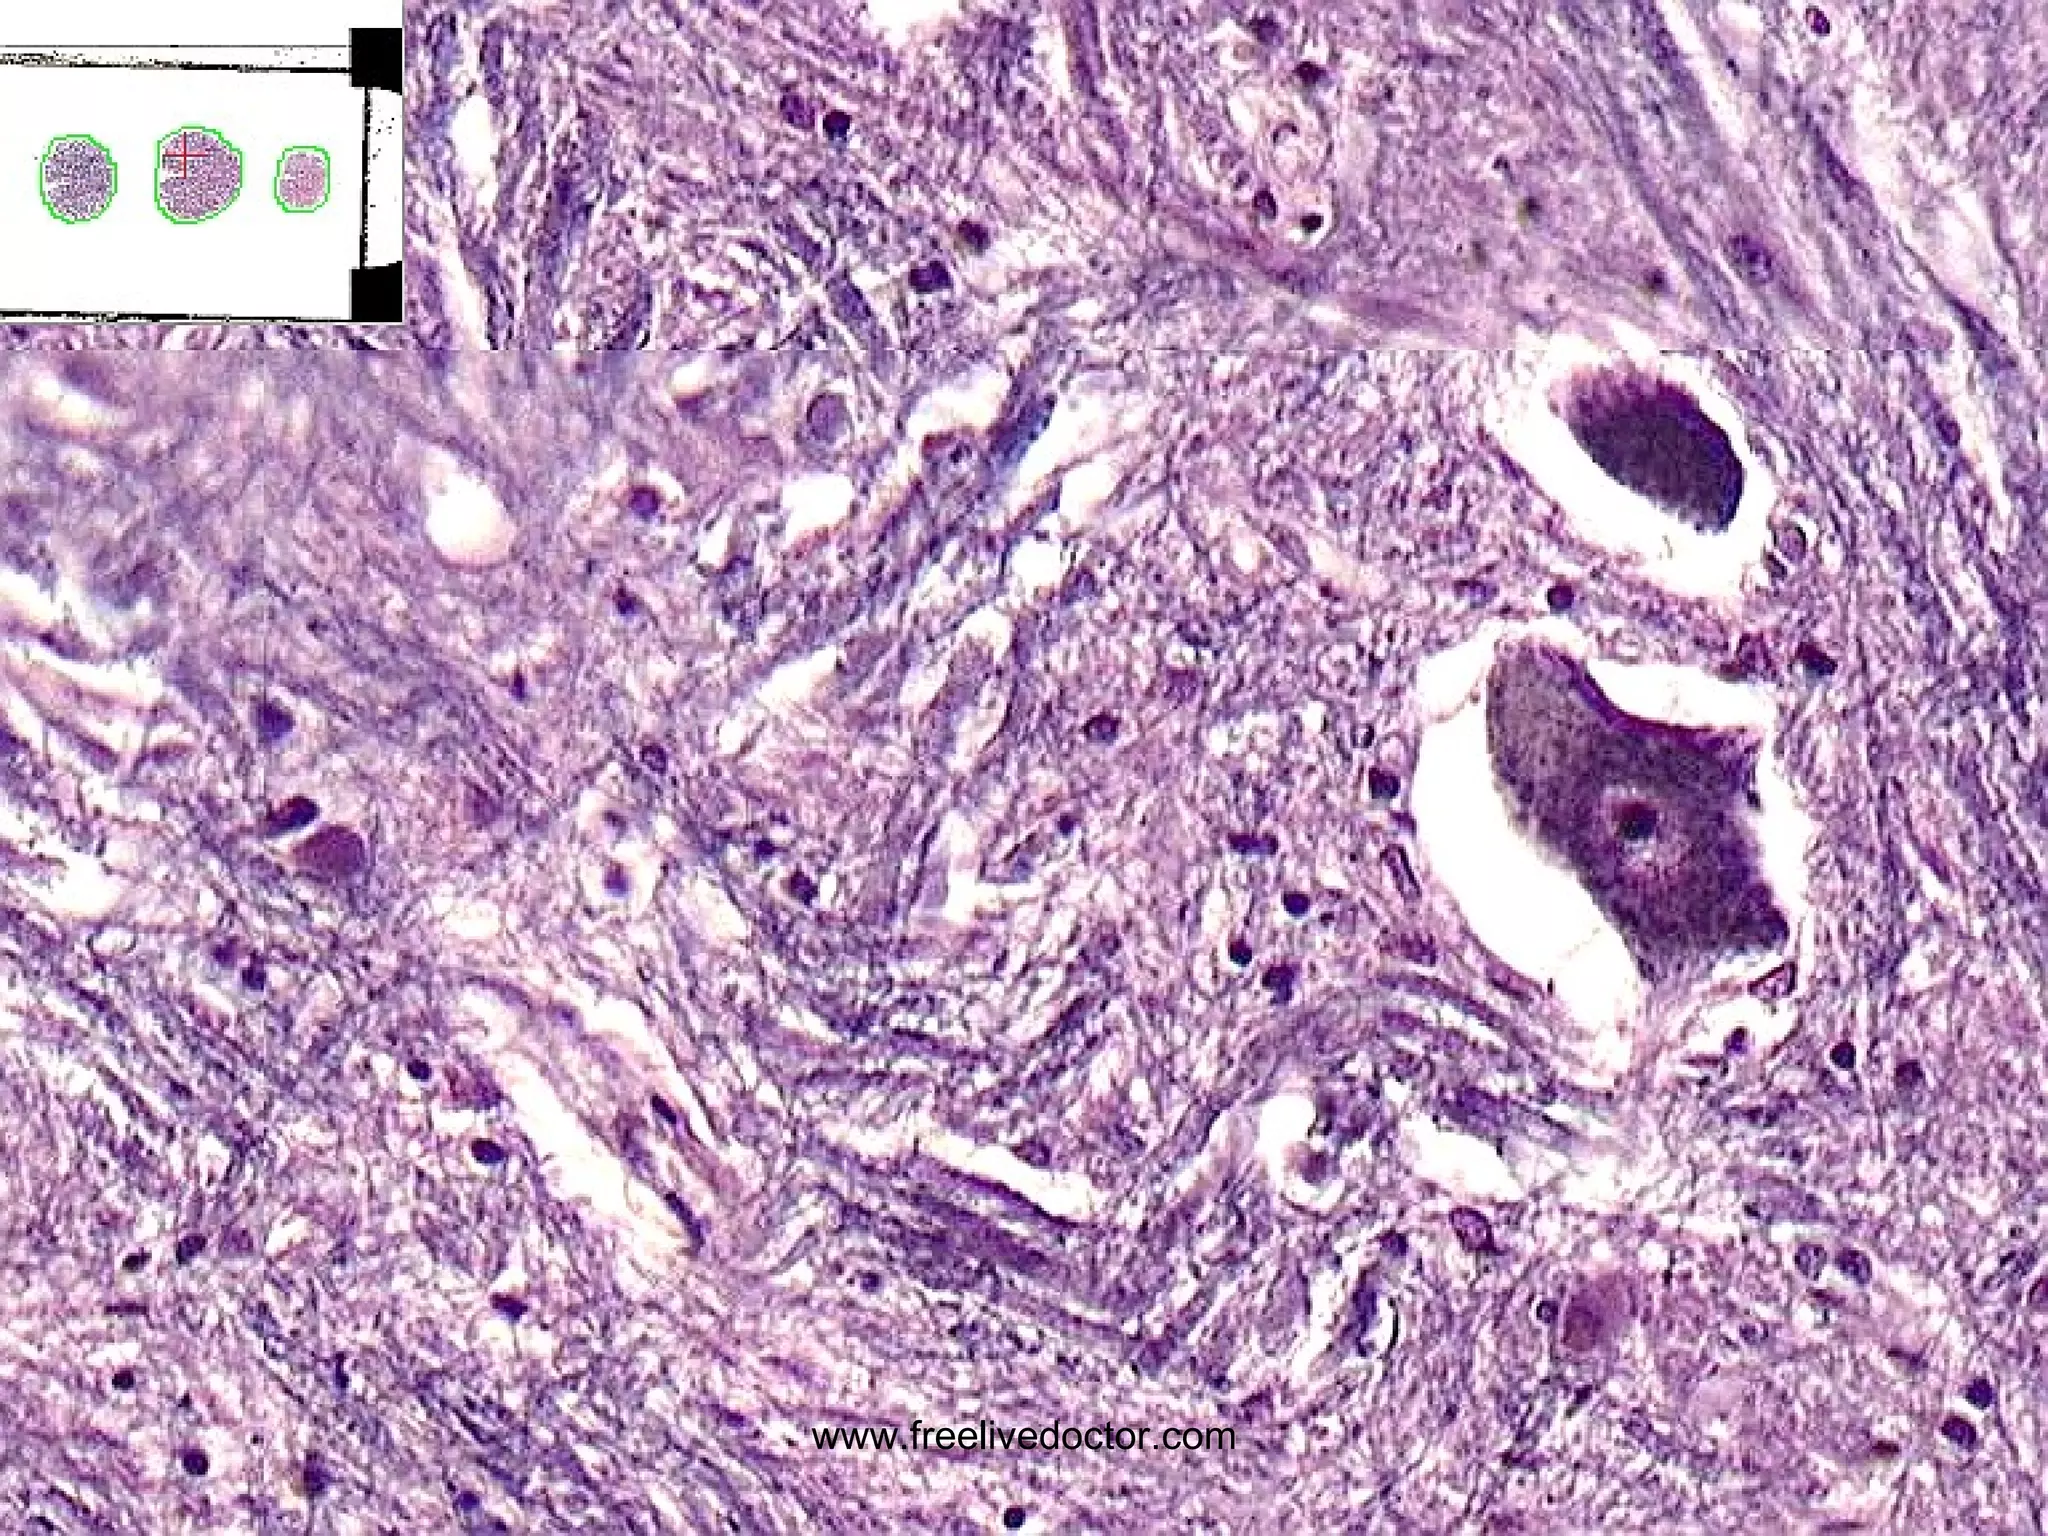

MENINGIOMAS Occur where dura is Very vascular BENIGN, but…. Can invade skull, etc. Only invade (displace) brain in areas adjacent to dura, i.e., parasagittal, falx, tentorium, venous sinuses Small, firm, and well defined like a SUPERBALL Often (usually?) have  PSAMMOMA   bodies www.freelivedoctor.com

• #162 Arts of this meningioma are denser than bone.

• #164 Psammoma bodies are diagnostic of meningiomas in brain tumors! What other kinds of tumors have psammoma bodies? Ans: papillary carcinomas, classically in thyroid